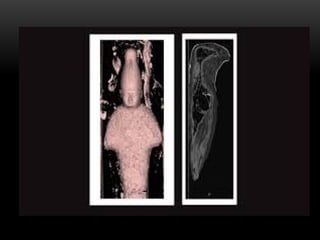

TOMOGRAFIA DOS PETS

TOMOGRAFIA DE MUNIAS